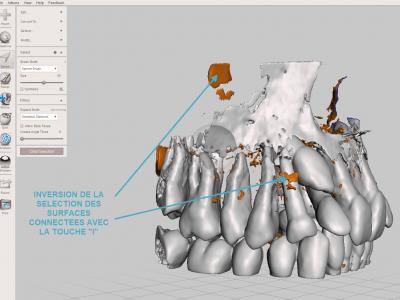

Pour éliminer les fragments non reliés : sélectionner une ou plusieurs petites zones à garder (dents par exemple) avec l'outil "Select" "Brush", puis opération "Expand to connected", puis inversion de la sélection avec la touche "I", puis les supprimer avec le raccourci clavier "X"